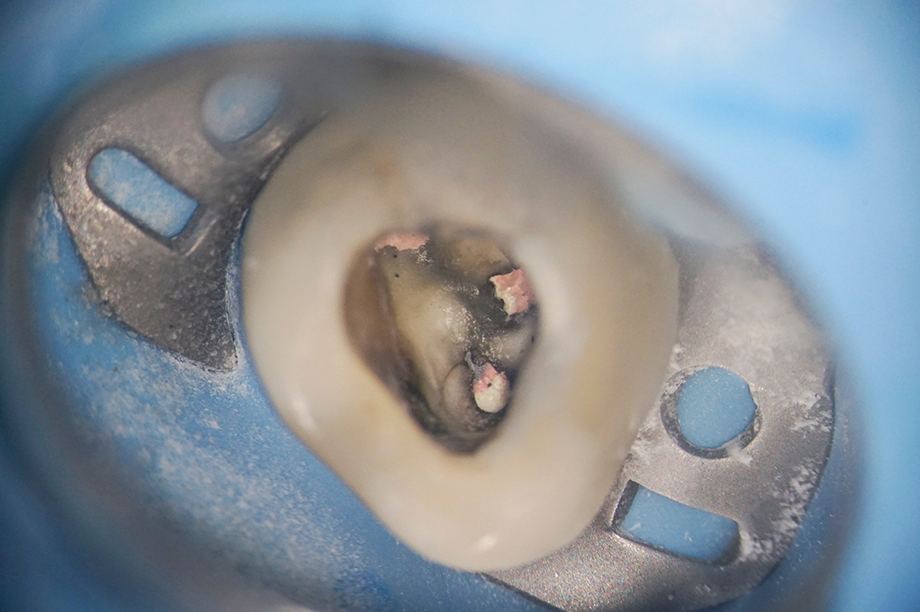

マイクロスコープの仕組みと視野

最大20倍程度の拡大視野

治療部位を肉眼の最大20倍程度にまで拡大し、高精度の光で照らし出すことができます。

これにより、これまで暗くて見えなかった歯の内部や、複雑な形状が、はっきりと歯科医師の目の前に映し出されます。

歯の根の治療(根管治療)

根管治療は、「歯を残す」ための最後の砦です。

歯の内部の根管は、髪の毛のように細く、複雑に枝分かれしているため、肉眼での治療成功率は低いとされています。

隠れた細菌を確実に取り除く

マイクロスコープは、根管の複雑な形状や、隠れた細菌の取り残しを鮮明に映し出します。